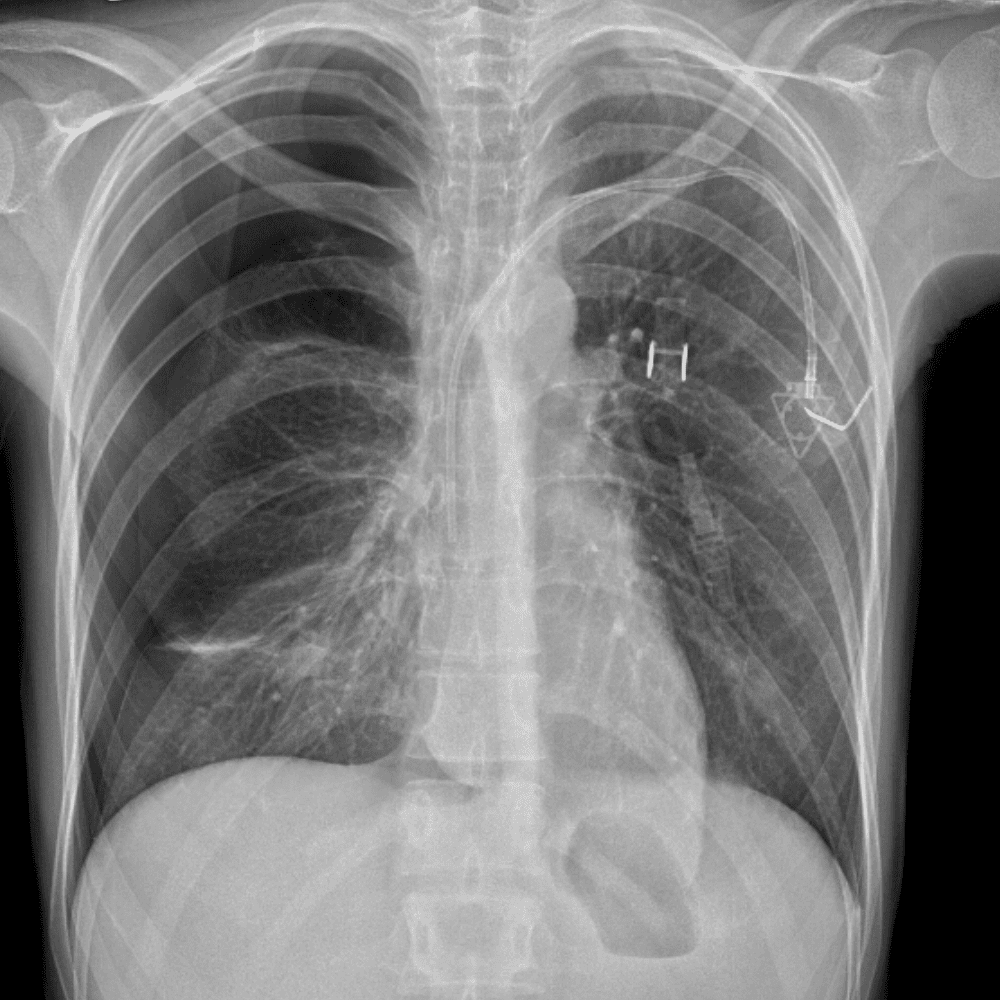

Practice Cases